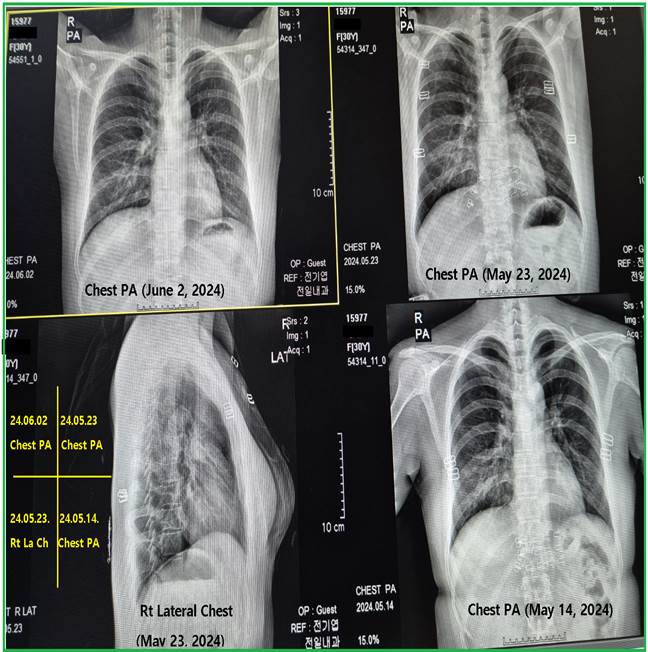

& Yazgi (2023). On the admission day

of May 14, 2025, she had a blood test and chest X-ray. Her blood chemistry

showed mild abnormalities with increased D-dimer/glucose/gamma-GTP levels of

0.64/170/56. Her chest X-ray revealed ground-glass opacities in both lower

lungs. Category 1 treatment of the healing protocols was initiated. This

treatment was carried out for 7 days, during which her persistent coughing,

weakness, mild fever elevation, and chest pain decreased. On May 21, 2025, her

blood was tested again. On May 23, 2024, she underwent a follow-up chest X-ray,

and she was discharged as her symptoms and chest X-ray had improved. However,

there was a discrepancy between the results of the blood toxicology test (Figure 3) at Jeon’s clinic and

the results of the blood chemistry tests and chest X-ray follow-up, which are

generally accepted in most hospitals and clinics. She was advised to undergo

category 2 and 3 treatments of the healing protocols after discharge. Her second

follow-up chest X-ray and blood toxicology tests were conducted on June 2, 2024

(Figure 3 & Figure 4).

Figure

3 On the

admission day of May 14, 2025, her blood chemistry showed some abnormalities

with elevated D-dimer/glucose/gamma-GTP levels of 0.64/170/56. Her untreated

blood in the first column of Figure 3 revealed: first, a graphene oxide-like mass (137

x 117 micrometers) and another graphene oxide-like mass (157 x 156

micrometers) with inflammatory cells and many actively moving microrobots;

second, multiple RBC rouleaux and a dough-like mixed mass (294 micrometers

long) of inflammatory cells and actively moving microrobots. Her chest X-ray

on May 14, 2024 (the Right Lower quadrant picture of Figure 4) indicated COVID-19 pneumonia in both lower lung

fields, showing ground glass opacities (GGO), despite her previous negative

PCR test in the prior city. On May 21, 2025, her

blood was tested. The blood toxicology test, as shown in the second column of

Figure 3, revealed the following:

first, there was a significant presence of inflammatory cells and GO

(graphene oxide measuring 362 x 271 micrometers); and second, there were

large dough-like mixed masses (one measuring 51 x 362 x 1,296 x 293 x 927

micrometers and the other 248 x 308 micrometers) consisting of inflammatory

cells and microrobots. General chemistry tests yielded normal results. On May

23, 2024, chest X-rays also showed improvement (the Right Upper quadrant and

the Left Low quadrant of Figure 4), with only remnants of

her GGO lesions visible. On June 2, 2024, her

blood toxicology test (the third column of Figure 3) and chest X-ray (upper

row, left column of Figure 4) were conducted, showing

improvements. |

Figure 4

|

4 Chest

X-ray on May 14, 2024, revealed ground-glass opacities (GGOs) in both lower

lung fields (lower row, right picture of Figure 4). After one week of

Category 1 treatment in the healing protocols, her follow-up chest X-rays

were reviewed on May 23, 2024. The ground-glass opacities in both lower lung

fields had decreased. (Chest PA: Upper row, right picture; Right Lateral

Chest X-ray: Lower row, left-side picture of Figure 4). She was discharged on May

23, 2024, and had a follow-up on June 2, 2024. Her chest X-ray (upper row,

left picture) showed nearly cleared ground-glass opacities (GGO) lesions in

both lower lungs. |